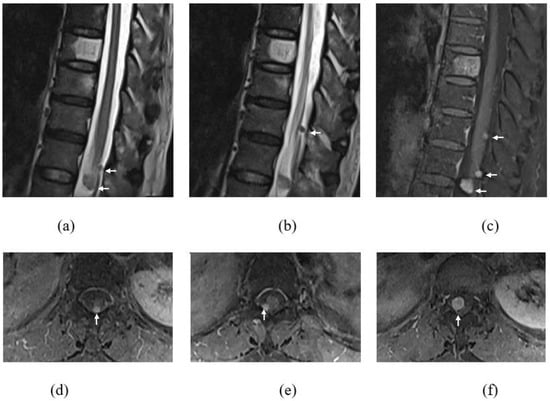

Figure 1.

T2WI (a,b) sagittal images of thoracic and upper lumbar spine showing multiple (white arrows) intradural extramedullary lesions at T11, T12 and T12/L1 levels. Gadolinum-T1FS sequence in sagittal (c) and axial (d–f) planes showing enhancement of all these lesions.